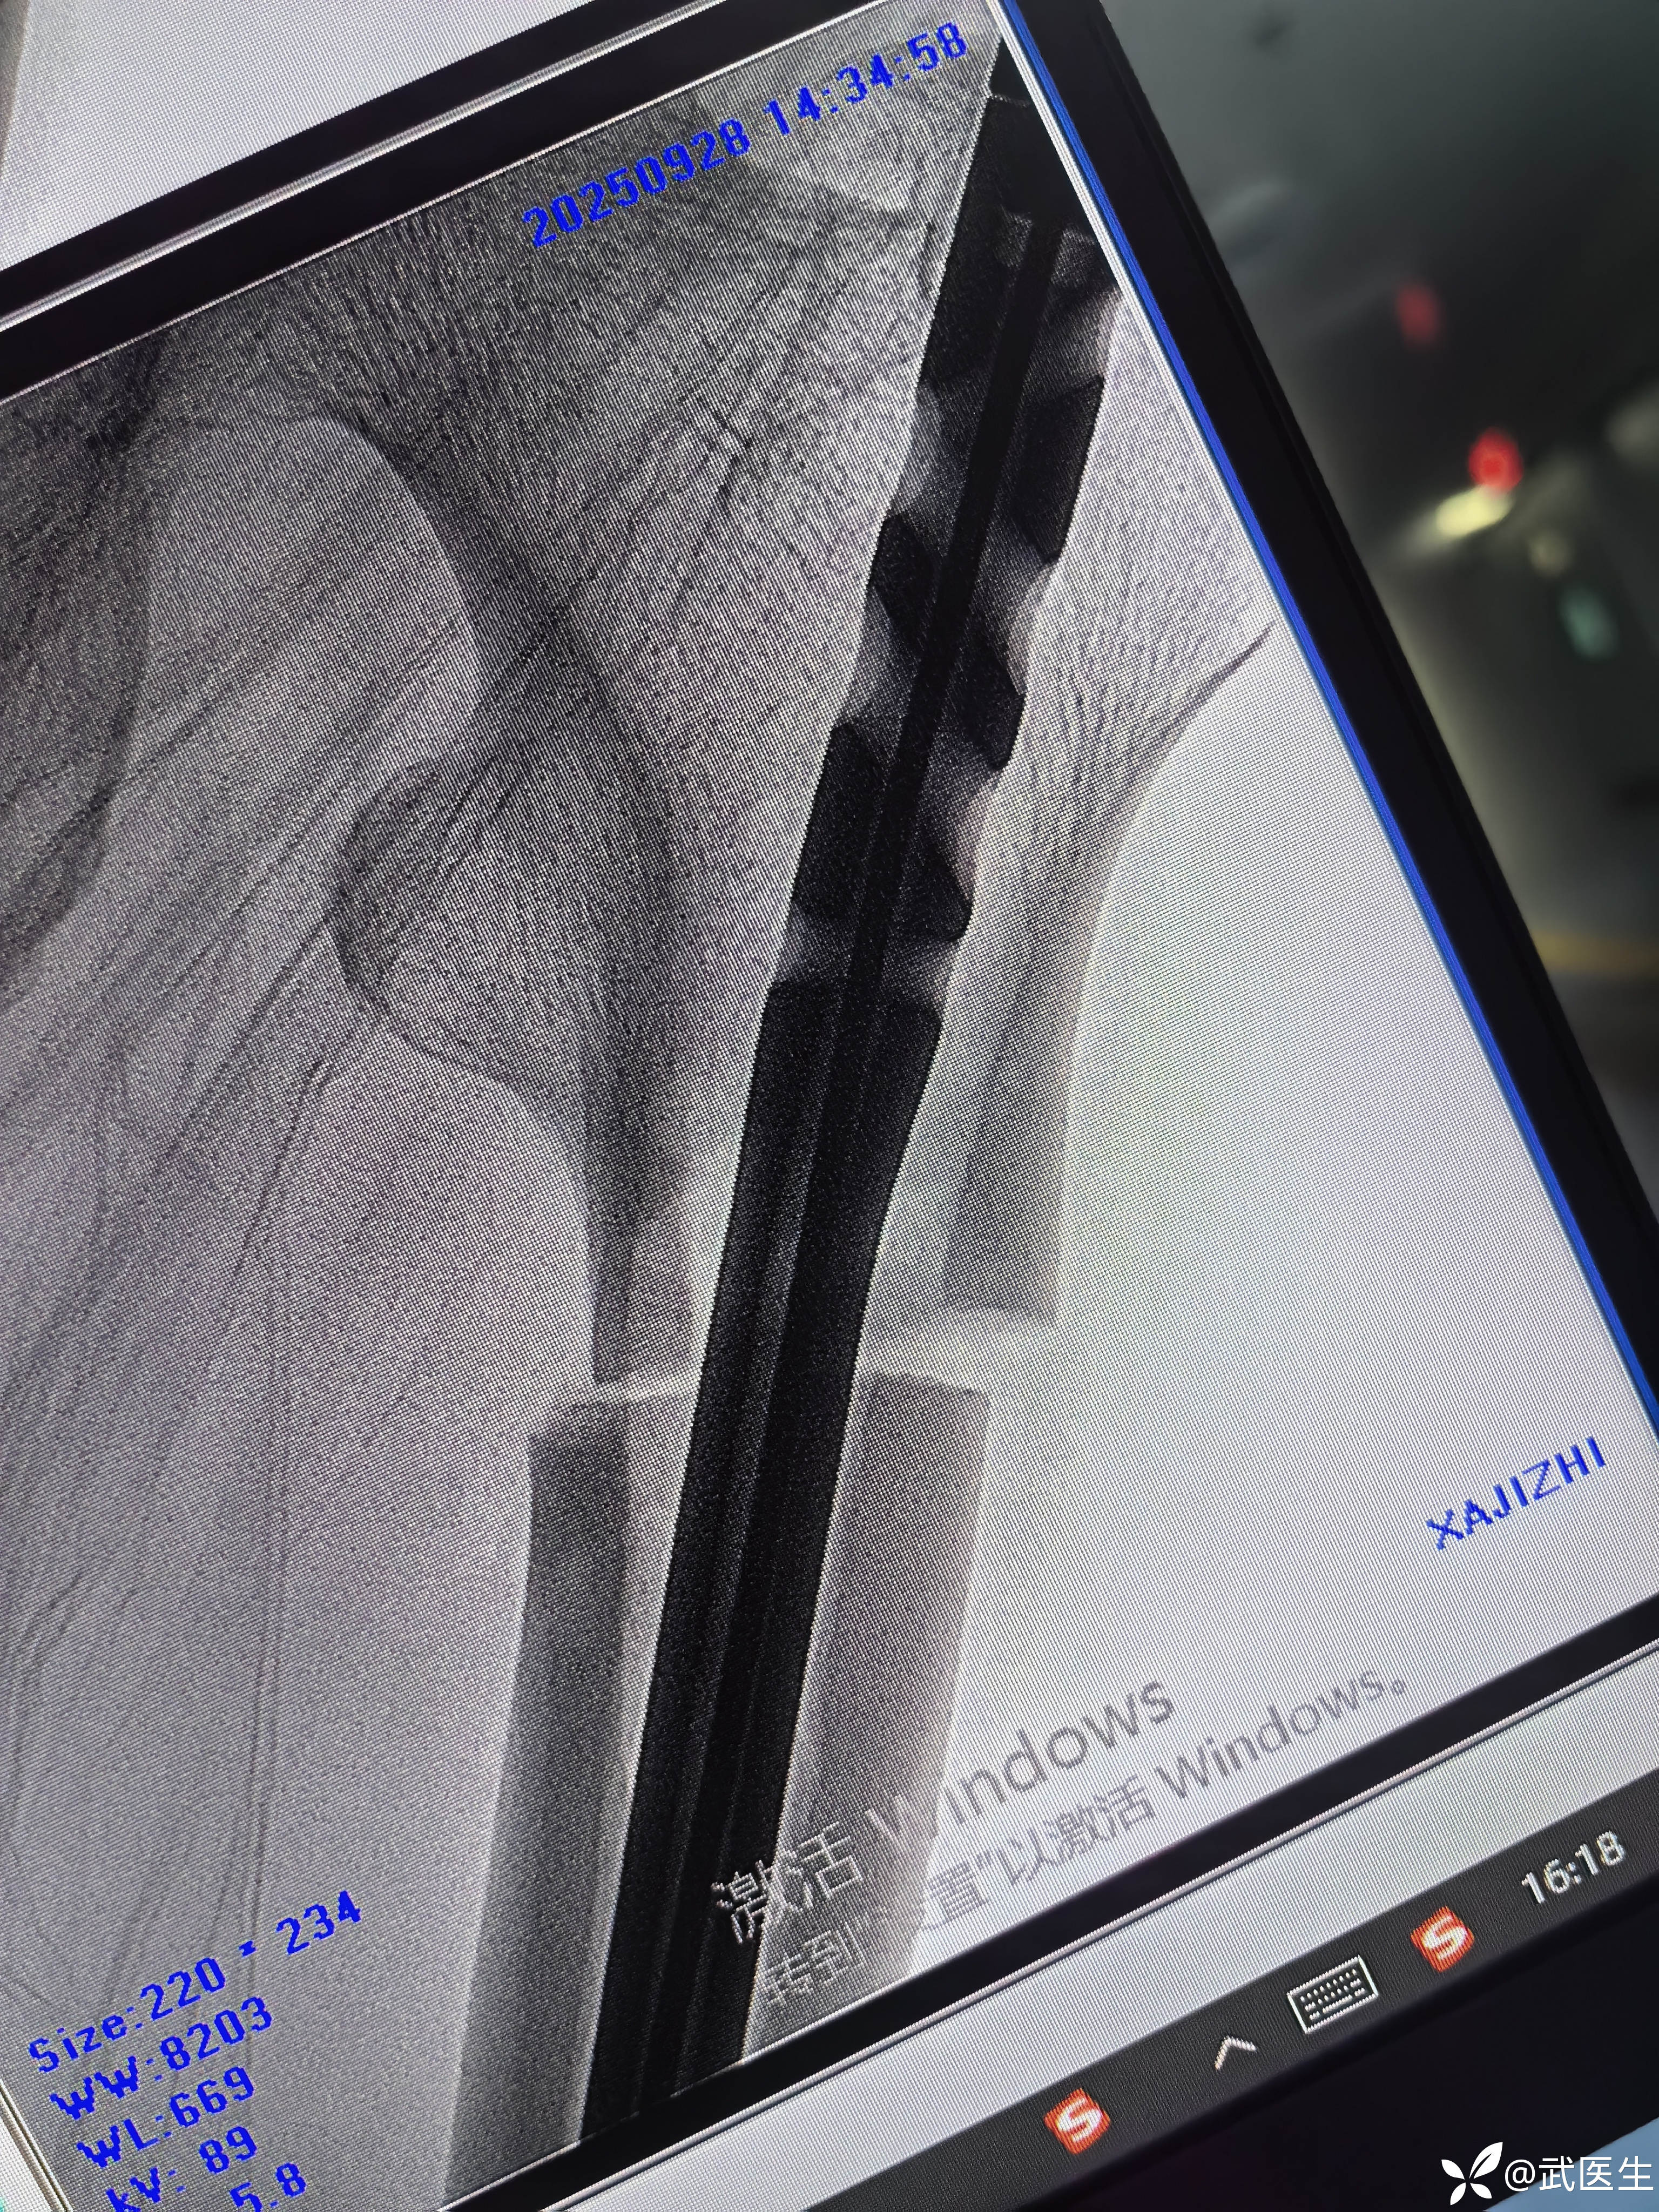

断端向外成角,对位不好,经常出现的问题,退出髓内钉,打阻挡克氏针,

置入

成角纠正,断端间隙有点大

捶足底,纵向挤压

间隙缩小

侧位前方出现蝶形骨块